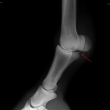

Fragment na spěnkové kosti